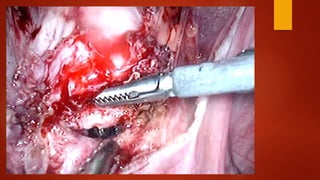

Суть метода После вскрытияпузырно-маточной складки брюшины и низведения мочевого пузыря при помощи монополярного электрода типа «Игла» рассекается рубец.

Края рубца «освежевываются»с помощью ножниц без использования энергий. Далее стенки матки ушиваются синтетической рассасывающейся нитью «Викрил» №1 отдельными швами в два ряда. Перитонизация.